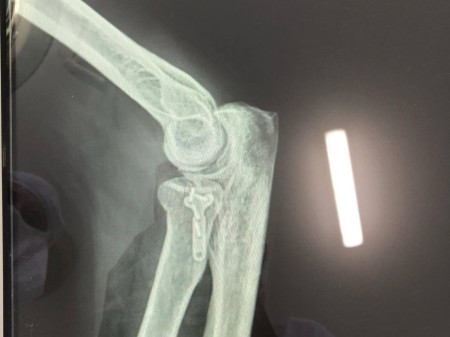

Після проведеного обстеження пацієнту було встановлено діагноз: перелом голівки променевої кістки, про це пишуть на фейсбук-сторінці медзакладу.

Хворому відновили конгруентність суглобових поверхонь та остеосинтез голівки променевої кістки. Операція пройшла успішно.

В операційній працювали: лікар-травматолог – Родзь Тарас Яремович; анестезіологічне забезпечення: лікар-анестезіолог – Пасічник Віктор Васильович; сестра медична операційна – Магдюк Людмила Анатоліївна.